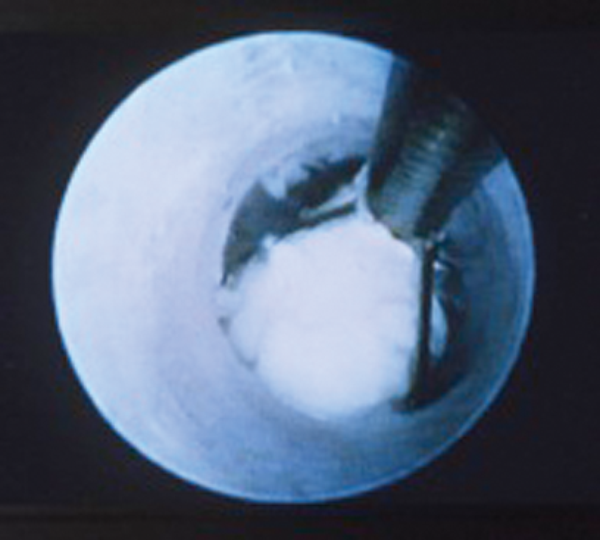

Figure 2: Image seen down a sialendoscope while capturing a stone in a basket.